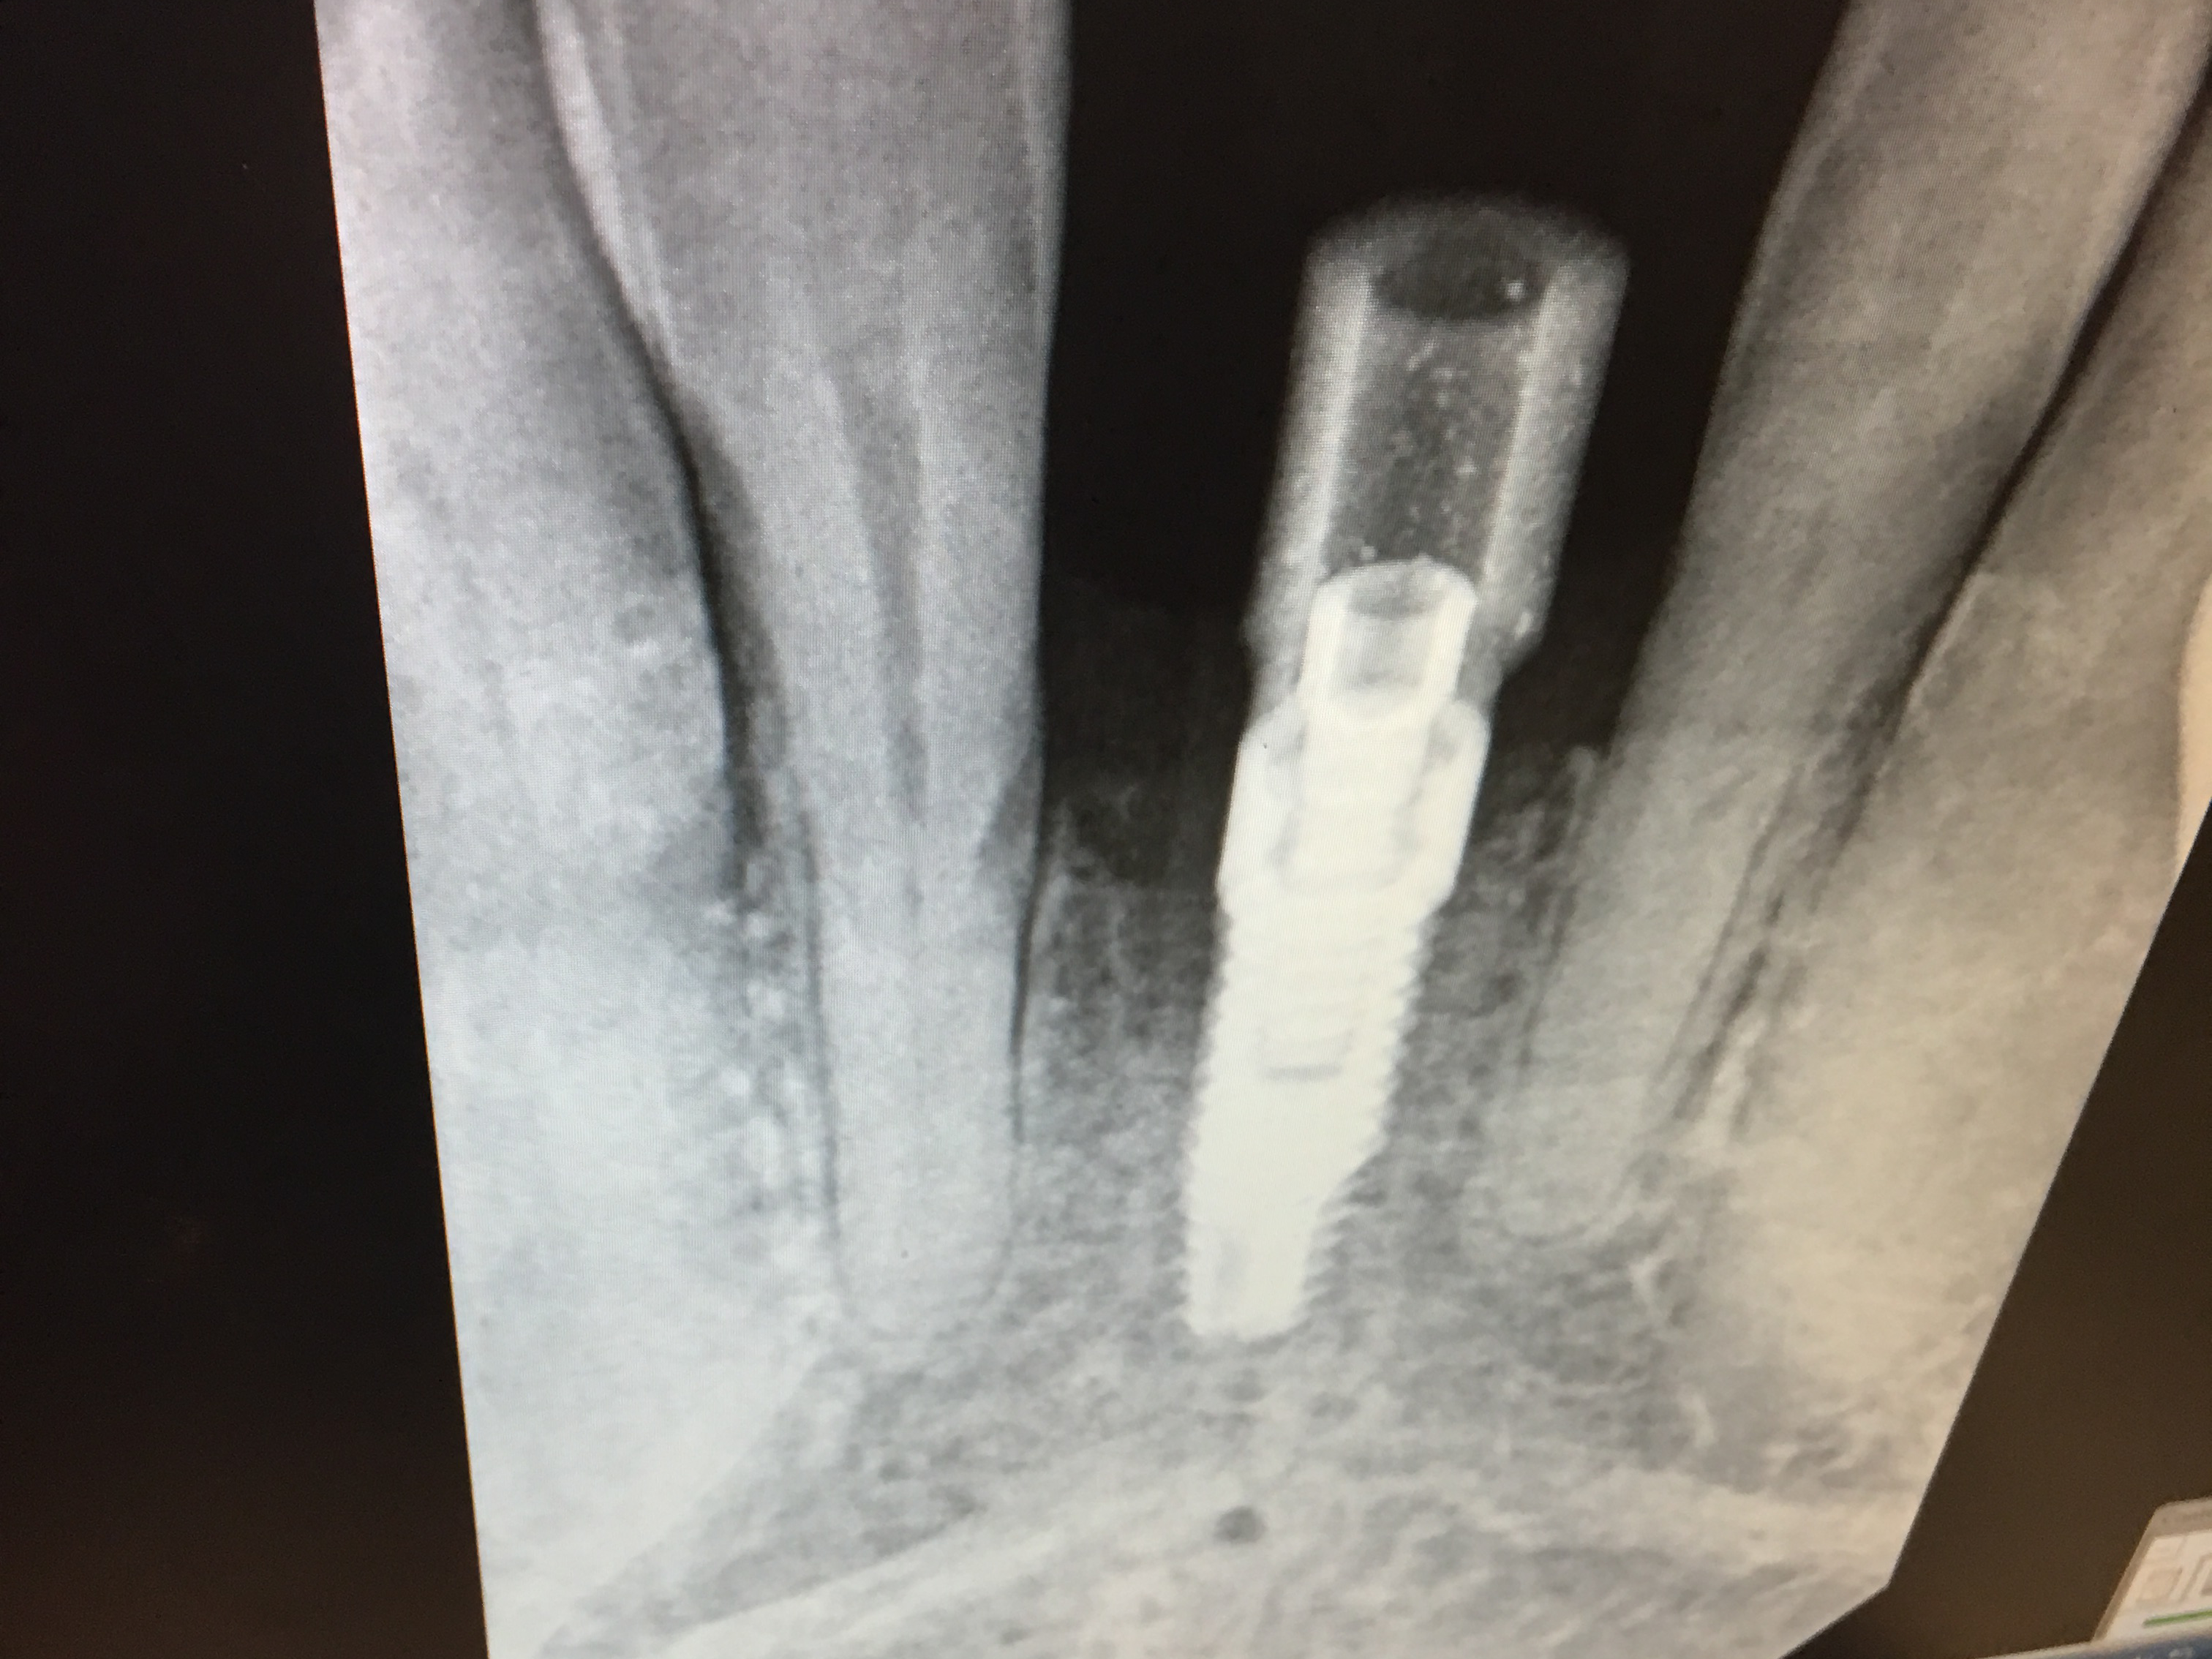

The North-East and Mid-Atlantic Regions hosted its first regional sales meeting on Dec 9 and 10.

The event included live surgery using Sweden & Martina Premium and Shelta implants, MISE sinus elevation kit, bone grafting, Ossix Plus membrane

and Sweden & Martina sutures.